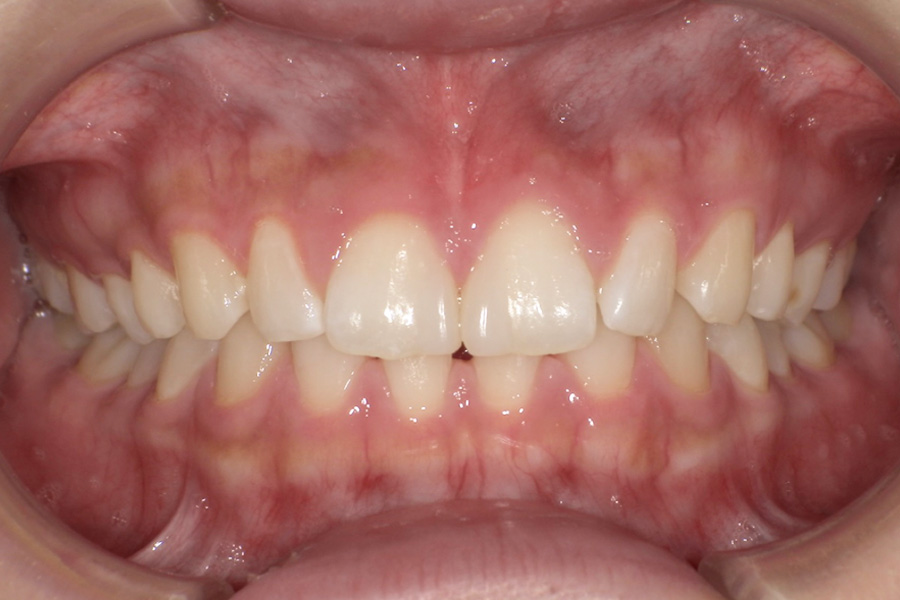

虫歯があるから削ったり悪くなったから抜くのではなく、まずは虫歯と歯周病が起きないようにより良い環境づくりをすること、そうすることによって歯を長く維持することが可能となります。

そのためには、健康状態に関する情報と生活習慣などの状況を把握したうえで、お口の中のリスク評価をおこないます。

その結果をもとに、お一人お一人にあった治療計画をご提案させていただきます。

ご自分の歯で食べ、話し、笑える幸せを生涯にわたり維持するためのお手伝いを全力でさせていただきます。